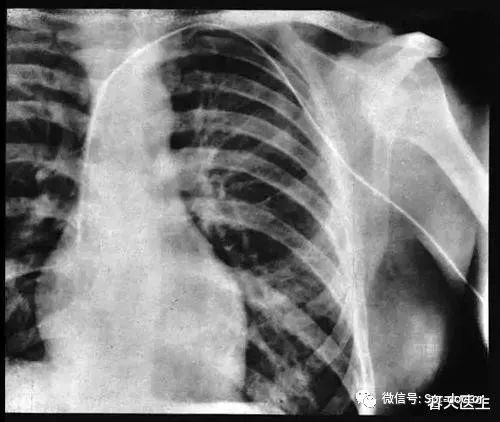

伊娃拍了两张片子 。 但这时导管还在肩膀附近 , 尚未抵达心脏 。 她暂停下来 , 福斯曼又往前推进了一些 , 直到触及右心房 , 导管尖端恰恰落在里面;第二张片子里 , 可以清楚看到尖端落在心脏 , 轻触着活体腔室 。